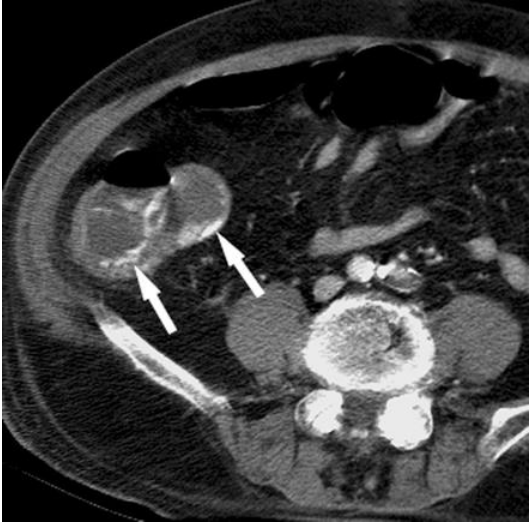

What can we see on CT angioography in a lower GI bleed into the bowel?

Blood with contrast goes into the bowel lumen